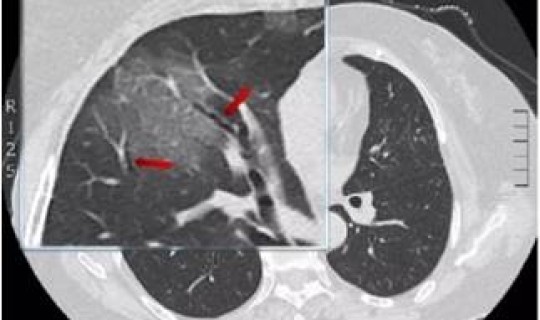

随着症状的加重,病人会出现呼吸困难、胸闷、气短,甚至会出现呼吸窘迫等严重症状 。进行影像学的检查会发现肺部有磨玻璃一样的肺间质的改变。表现严重的还会出现脓毒血症 、感染性休克、凝血功能障碍和肾功能衰竭等。

(图片来源于 *** 侵删)